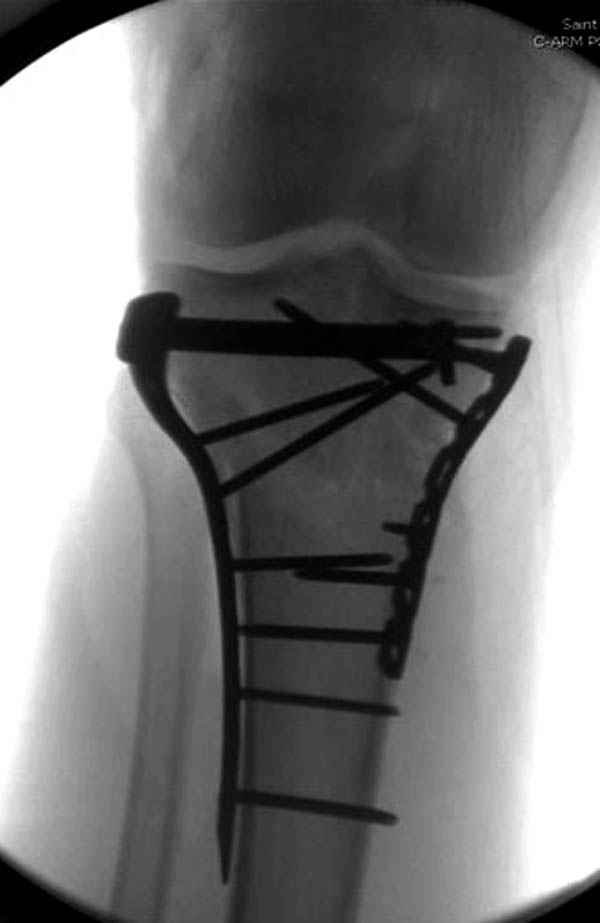

Уважаемые коллеги! В прошлую пятницу больной прооперирован - как и планировалось мыщелковая LCP от ChM. Малоинвазивно не получилось - один большой доступ :(. (но с минимальным скелетированием б/б кости). Наружный мыщелок собрали, но по контролю видно, что задне-медиальный отдел метаэпифиза смещен. Фиксировать не стали (?). 4-е сутки после операции - по м/тканям без проблем. Дополнительная иммобилизация синтетическим тутором.

Интересно услышать ваши мнения, анализ ошибок...

P. S. перелом диафиза на контроле не совсем захвачен, но проблем там нет. Приношу извинения за низкое качество Р-грамм - выполнены на сканере (фотоаппарат не работает :)) .

Трудно поверить, что разрекламированная Ортопедическая школа Восточной Украины позволяет такие странные снимки? На прямом снимке сохранен общий контур плато, но не известна судьба импрессии суставной поверхности. На полубоковой?, оставлен без репозиции задне-медиальный отдел, и навряд ли после такой фиксации можно удовлетвориться результатом.

Такая ситуация характерна для многих, когда принимается ошибочное решение, т.е пытаются фиксировать одним имплантом переломы двух мыщелков. Латеральная пластина приемлема только для тех случаев, когда сохраняется интактным медиальный диафизарный кортекс и отсутствует фрагментация на верхушке медиального перелома.

Здесь как раз тот случай, когда результат зависит не только от мастерства хирурга, но и от наличия современных методов исследования. Например, КТ которая поможет рассчитать направления шурупов и установку импланта. Кроме этого, поможет определиться с доступом.

На представленных предоперационных срезах КТ огромный задне-медиальный фрагмент расположен больше кзади, чем медиально. Для планирования, кроме поперечных срезов, надо ориентироваться на корональные срезы, которые укажут топографию верхушки медиального фрагмента.

При сложных переломах тибиал плато для своего рода Damage Control мы иногда применяем поэтапную тактику. Сперва оперируется одна сторона, а потом после рекондиции мягких тканей окончательный этап.

Если состояние мягких тканей позволяет, я бы предложил такой метод для вашего больного. Без предварительного планирования будет трудно, но шанс не надо упускать. Всего несколько дней после операции, и такая тактика лучше, чем недовольный молодой пациент.

Представленные снимки не информативны, нужны отдельные качественные снимки коленного сустава и голени без ротации.

Доступ к медиальной стороне задний или медиальный, через pes или в пространстве между medial gastroc мышцы.

Надеюсь, представленные снимки разных случаев помогут разобраться в тактике, и критика примется без личной обиды.